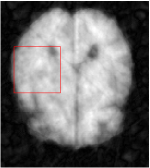

Qualitative comparison between conventional and Meta-learning methods are shown in Figure 1 and 3, which display the reconstructed MR images of the same slice for T1 and T2 respectively, we label the zoomed-in details of HGG in the red boxes. We observe the evidence that conventional learning is more blurry and lost sharp edges, especially in lower CS ratios. From the point-wise error map, we find meta-learning has the ability to reduce noises especially in some detailed and complicated regions comparing to conventional learning.

In general supervised learning, training data need to be in the same or similar distribution, heterogeneous data exhibits different structure variations of features which hinders CNNs to extract features efficiently. In our experiments, raw measurements sampled from different ratios of compressed sensing display different levels of incompleteness, these undersampled measurements do not fall in the same distribution but they are related. Different sampling masks are shown at the bottom of Figure 1 and 2 may have complemented sampled points, in the sense that some of the points which sampling ratio mask does not sample have been captured by other masks. In our experiment, different sampling masks provide their own information from their sampled points so that four reconstruction tasks help each other to achieve an efficient performance. Therefore, it explains the reason that Meta-learning is still superior to conventional learning when the sampling ratio is large.